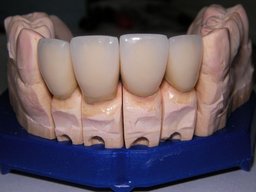

Links die Kronen aus dem Dentallabor "Heitmeyer Zahntechnik", Osnabrück. Man sieht praktisch keinen Metallrand. Der Patient war zur Farbbestimmung im Dentallabor - so halten wir es praktisch immer. Rechts das Ergebnis bei der 1. Nachkontrolle am 27.3.05. Das Zahnfleisch muß sich noch etwas erholen.